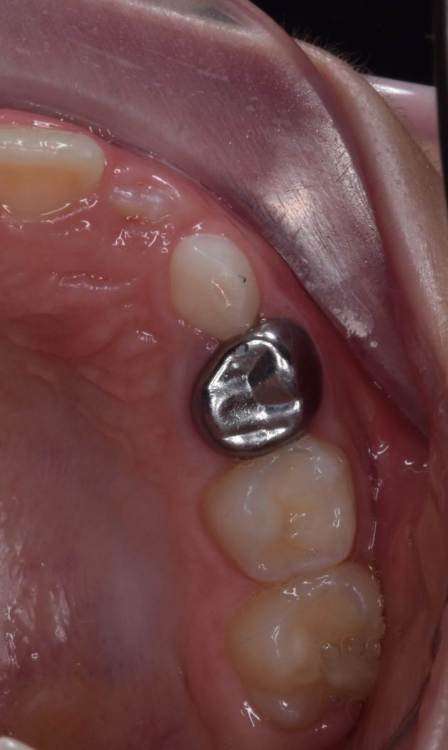

CRAZYDUCK Опубликовано 30 июня, 2022 Автор Поделиться Опубликовано 30 июня, 2022 Пример лечения обратимого пульпита 7.5 зуба . 2 1 Ссылка на комментарий